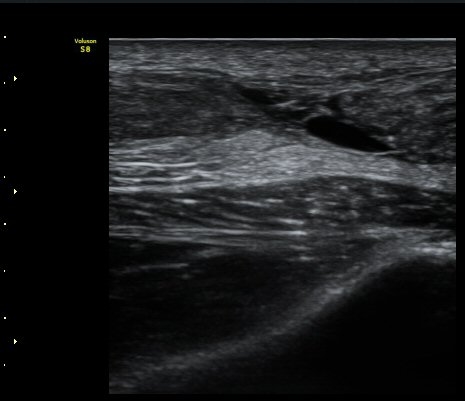

ÃÊÀ½ÆÄ °Ë»ç